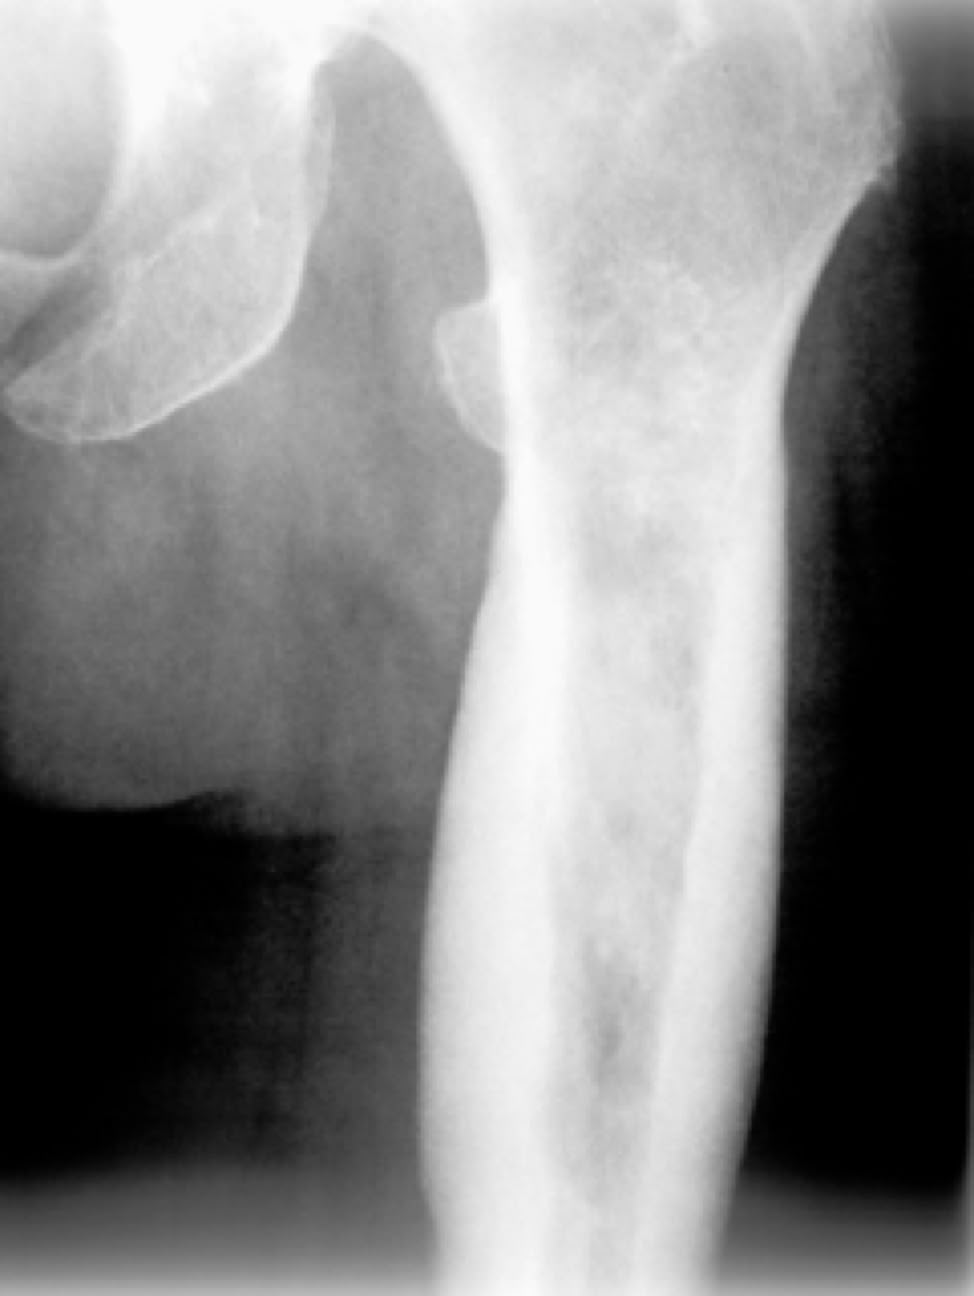

Leider besteht auch einiges an Erfahrung mit Knochen- und Weichteiltumoren.

Tumor femur